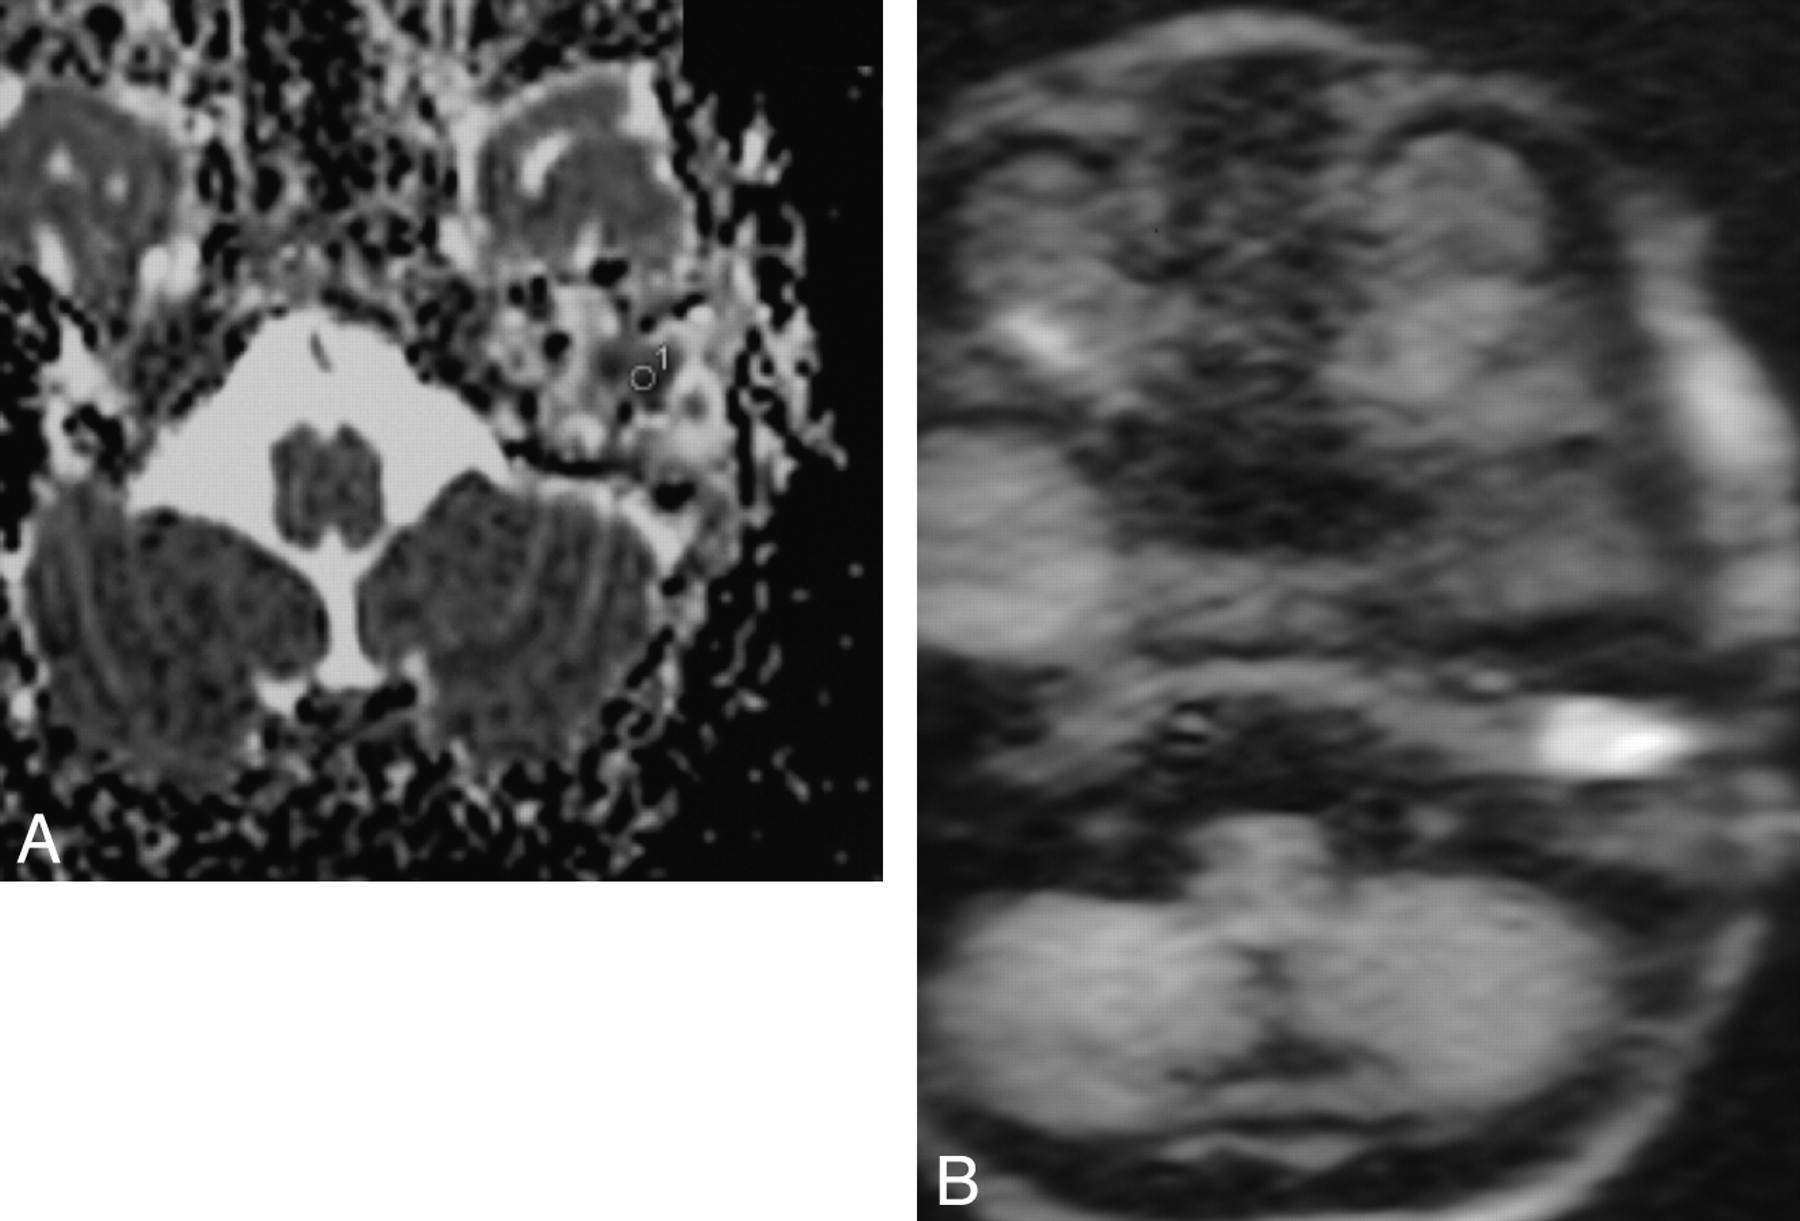

All examinations were reviewed by a radiologist who had 15 years’ experience in middle ear imaging. For each patient, this radiologist calculated the ADC value in a selected region of interest on the cartography on the Avanto workstation (Siemens) (Fig 1). These regions of interest were placed in an area matching the suspected cholesteatoma or abscess of the middle ear according to the usual sequences and were approximately 11 mm2 in volume.

A, ADC value cartography and region of interest to calculate ADC value. B, DW image.